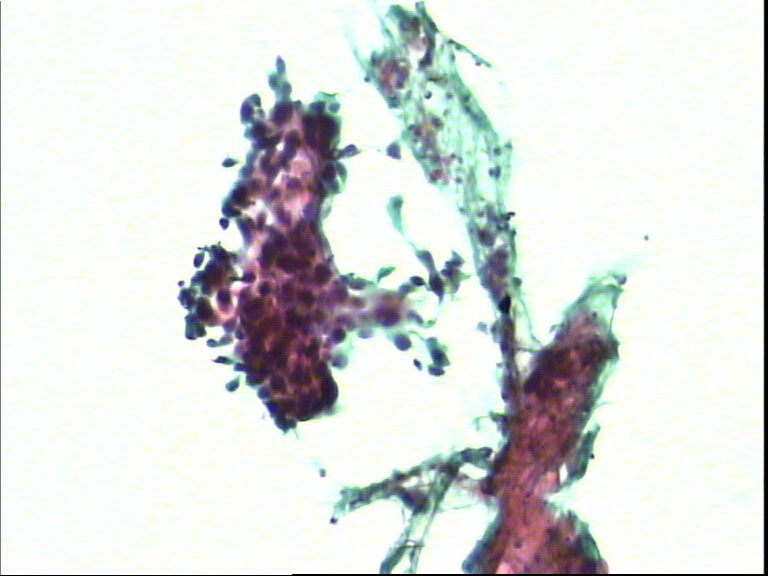

宫颈液基,老年妇女,78岁,临床:宫颈肥大

• 宫颈液基,老年妇女,78岁,临床:宫颈肥大图4

图4

HSIL,建议活检。

HSIL,疑SCC。

HSIL,不除外SCC建议活检。

宫颈高级别上皮内病变,不除外鳞状细胞癌(建议活检)。

呵呵,最后三张就是普通的刮片